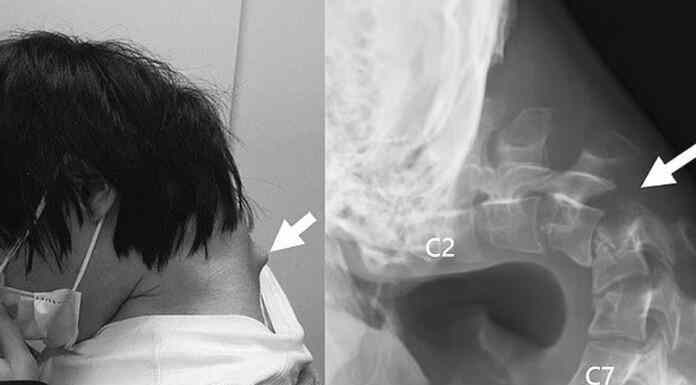

25χρονος Ιάπωνας gamer απέκτησε παραμόρφωση στον αυχένα- «σύνδρομο πτώσης κεφαλής» από την υπερβολική χρήση κινητού!

Ιάπωνες γιατροί κατέγραψαν μια εντυπωσιακή αλλά ταυτόχρονα ανησυχητική περίπτωση 25χρονου...